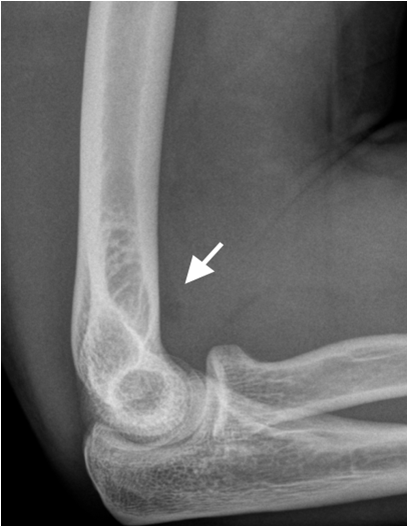

Since x-ray films are projection images of three-dimensional structure a second imaging plane, usually perpendicular to the initial exposure is mandatory to fully assess the three-dimensional structure. In complex anatomic regions additional oblique projections or function tests may be necessary (head of radius, shoulder, pelvis, spine).

Fig. 3. Split fracture of the radial head. The fracture is clearly seen on the oblique image (right image) whereas the fracture is almost invisible on the lateral view (left image). The displaced fat pad (white arrow) indicates joint effusion and is an indirect sign of significant trauma.